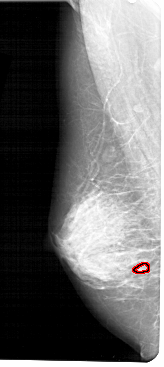

FILE: A_1280_1.LEFT_MLO.OVERLAY

TOTAL_ABNORMALITIES 1

ABNORMALITY 1

LESION_TYPE CALCIFICATION TYPE PLEOMORPHIC DISTRIBUTION CLUSTERED

ASSESSMENT 4

SUBTLETY 2

PATHOLOGY BENIGN

TOTAL_OUTLINES 1

LEFT_MLO LINES 5491 PIXELS_PER_LINE 2446 BITS_PER_PIXEL 12 RESOLUTION 43.5 OVERLAY